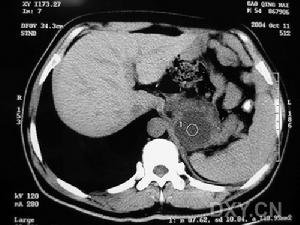

5.其它:有些患者中可發現子宮纖維瘤或腎血管平滑肌脂肪瘤,肺功能改變:常為阻塞型通氣功能障礙和彌散功能障礙。

是診斷淋巴管平滑肌瘤的重要手段。胸部CT尤其是HRCT可以明確顯示出普通胸片顯示不清的肺囊腫。淋巴管平滑肌瘤的肺囊腫具有顯著特點,為全肺均勻分布的大小不等的薄壁囊腫,直徑在0.5~5cm之間,囊壁的厚度一般<2mm。早期囊腫較小,隨病情發展囊腫加大。這類形態的囊腫發生率為100%,是診斷淋巴管平滑肌瘤的重要依據。早期約50%患者出現磨玻璃影。在CT上能看到結節陰影者僅5%左右,為腫大的囊腫壓迫周圍過度生長的平滑肌細胞所致。如出現片狀陰影則提示出血。Sherrier等報告的8例LAM患者中4例發現縱隔淋巴結腫大。以HRCT定量測定囊腫面積與測定肺容量、彌散功能、運動試驗所評價的疾病嚴重程度相符合,故HRCT即可用於診斷又可判定預後。CT或HRCT可發現腹後壁、腹腔、腎臟、盆腔的病變。